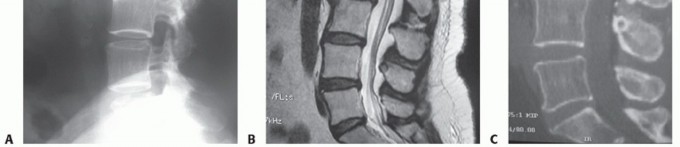

Lateral radiographs allow for measurement of the intervertebral disc height and allow comparison to other lumbar intervertebral discs (FIG 2A).

MRI provides excellent visualization of the discs, the degree to which they have degenerated, and the relationship of the discs to the adjacent endplate and surrounding neurologic structures (FIG 2B).

Computed tomography (CT) discography provides more detailed information about the disc morphology after contrast administration (FIG 2C).

FIG 2 • A. Lateral radiograph showing DDD at the L2-L3 level. B. Sagittal T2-weighted MRI of the same patient with low signal intensity in the nucleus of the L2-L3 disc. Anterior and posterior disc bulges are present. C. Sagittal CT discogram of the same patient showing dramatic loss of integrity of the L2-L3 nucleus and annulus with leakage of contrast anteriorly. The patient's pain was concordant at the L2-L3 disc level. The L1-L2 and L3-L4 discs served as negative controls with regard to both disc architecture and pain.*